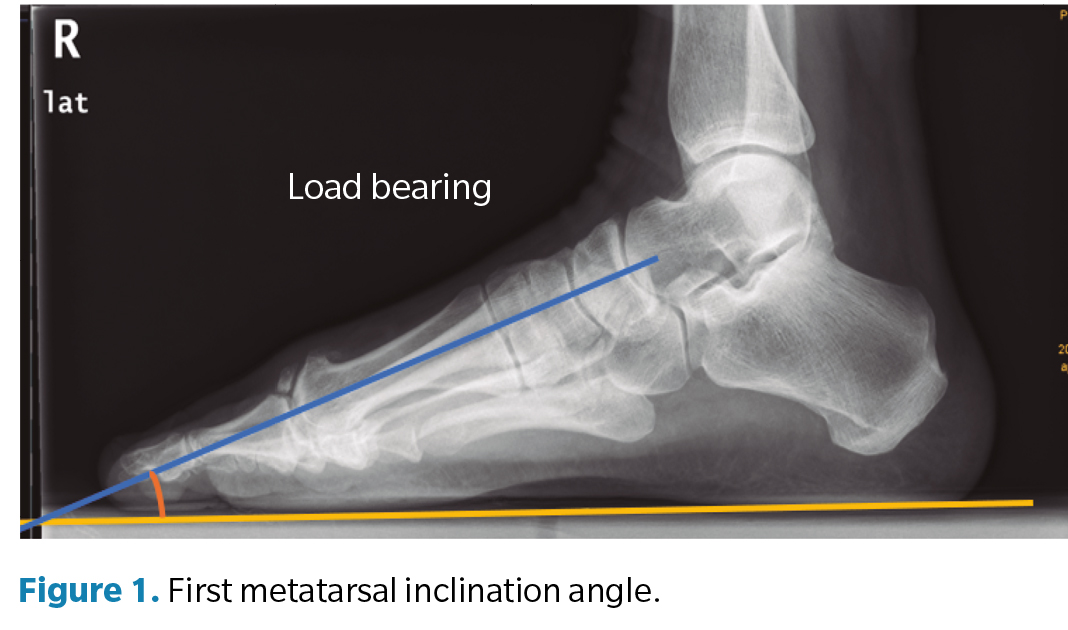

Regarding the goniometric variables in the lateral X-ray, the following angles were obtained: first metatarsal inclination angle, calcaneal inclination angle, Meary-Tomeno line, and internal Costa Bartani angle. The metatarsal inclination angle or Fick angle involves the inclination of the 5 metatarsals; however, for this study, only the inclination angle of the first metatarsal was considered (Figure 1), which was defined by the diaphyseal axis of the first metatarsal with the horizontal plane of the ground support11. The calcaneal inclination angle (Figure 2) is defined by the axis of the calcaneus, a line connecting the calcaneal tuberosity to the plantar margin of the anterior extension of the calcaneus near the calcaneocuboid joint, and the support plane (line formed by the proximal plantar tuberosity of the calcaneus and the head of the 5th metatarsal). A value of 20° is considered normal(12). The Meary-Tomeno line (Figure 3) is defined as the line passing through the axis of the talus (bisector of the angle formed by the tangent to the superior and inferior borders of the talus) and the axis of the diaphysis of the first metatarsal13). The internal Costa Bartani angle (Figure 4) is defined as the union of 3 points: the lowest point of the medial sesamoid, the lowest point of the posterior tuberosity of the calcaneus, and the lowest point of the talonavicular joint(14)..